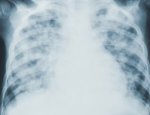

Названы нетипичные симптомы рака легкого

По словам врача-онколога Суны Исаковой, одним из нетипичных симптомов рака легкого может быть чувство тошноты или увеличение веса с неравномерным распределением жира.

В интервью Исакова рассказала, что рак легкого может проявляться разными симптомами, порой – нетипичными.

«Иногда первым симптомом рака легкого может быть увеличение надключичного лимфоузла, редко опухлость, синюшность лица, неврологические симптомы. Может также наблюдаться опущение верхнего века и сужение зрачка со стороны поражения», - сообщила онколог «Газете.Ru».

В некоторых случаях, добавила Суна Исакова, первым внешним признаком заболевания может быть чувство тошноты, слабость. Кроме того, у заболевшего человека возможны судороги, или он прибавляет в весе, при этом происходит неравномерное отложение жира.

Что касается более очевидных и известных симптомов этого вида рака – кашля, боли в груди, одышки, осипшего голоса – они чаще возникают на последних этапах заболевания.